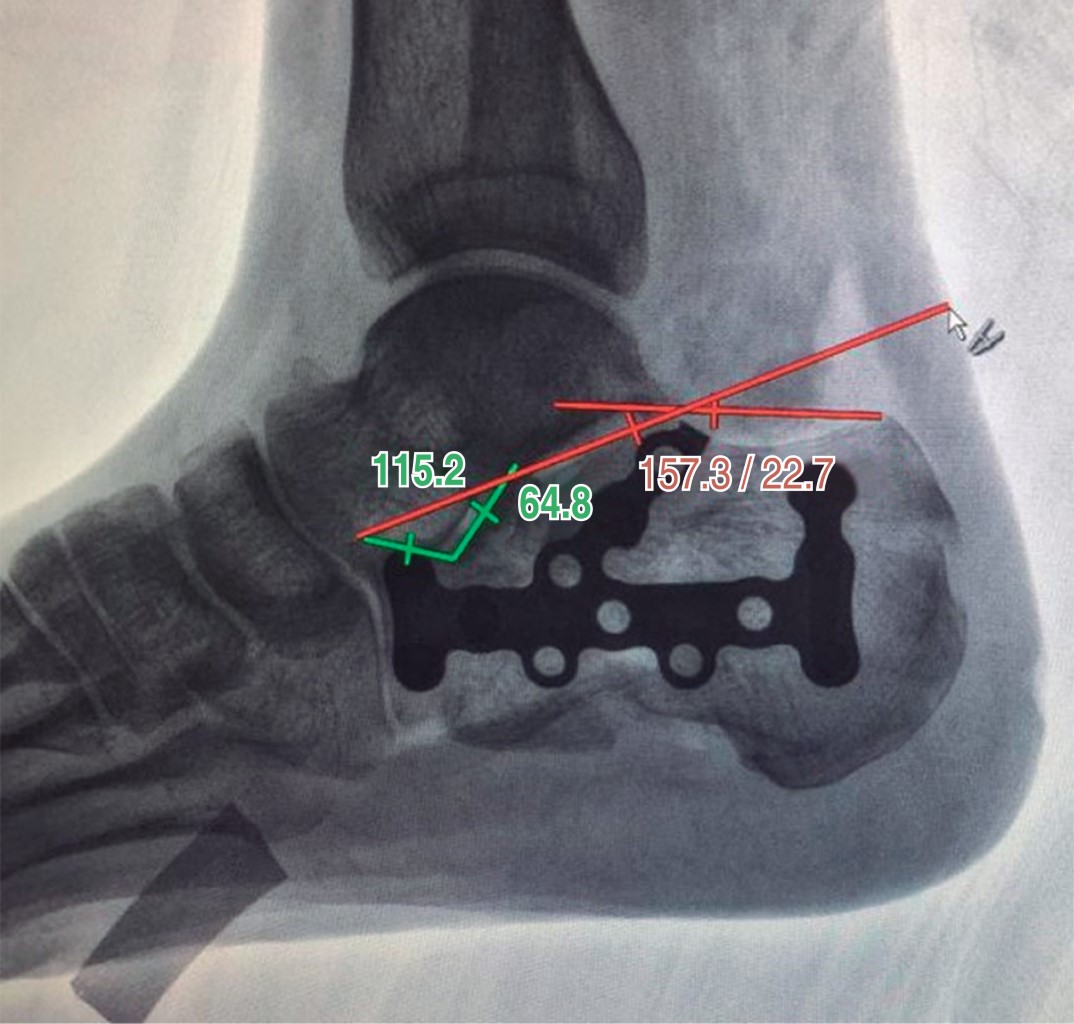

Figure 1